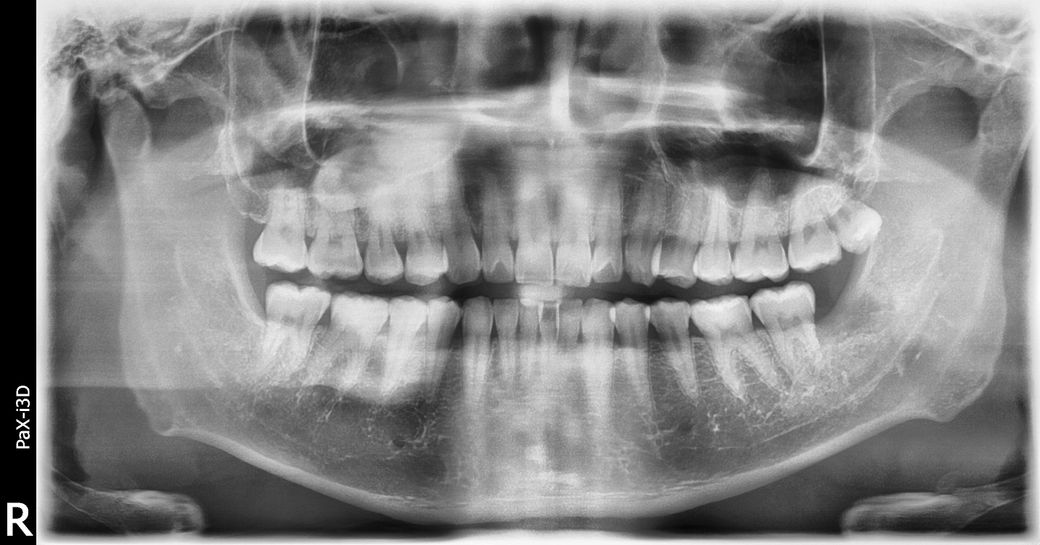

• 사랑니 발치 후

• 1번 째 사진

• 2번 째 사진

• 3번 째 사진

좌측 상악 사랑니는 발치가 안된거 같습니다. 이부분은 환불을 문의 하셔서 받으셔야될것같습니다 .

좌측 상악의 사랑니가 남아 있습니다 사랑니를 뽑지 않았다면 나중에 뽑아도 되기 때문에 치료를 받았던 치과에서 문의를 해 보는 것이 좋습니다

왼쪽 위 사랑니 (사진상 오른쪽 위) 는 그대로 남아있네요.

진료내역상 보면 위,아래 사랑니 발치가 2개를 한 것이 맞으므로 이는 문제가 될 수 있는 부분입니다.